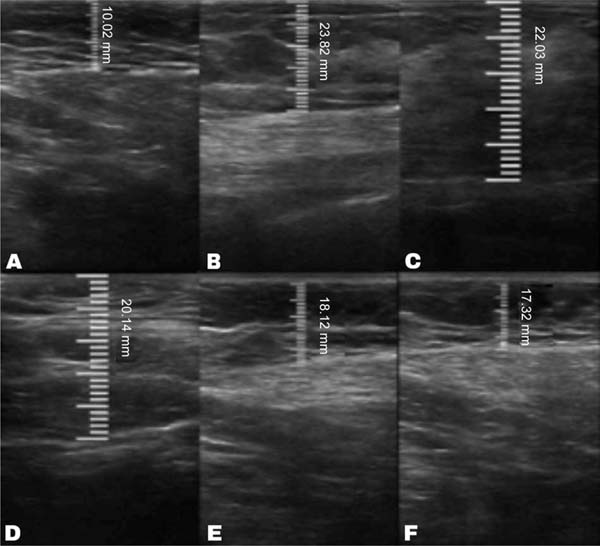

The average volume of fat grafted was 116.7 mL in the decanted graft group and 123.3 mL in the filtered graft group. The average initial thickness of the subcutaneous tissue was approximately 11 mm in both groups. This value increased to 22 mm in the immediate postoperative period in the decanted group and 23 mm in the filtered group.

Both groups presented progressive reabsorption. ►Table 1 and ►Fig. 5 show the change in mean subcutaneous thickness in both groups.

| Operative period | Decanted graft group (n=6) | Filtered graft group (n=6) |

|---|---|---|

| Preoperative | 11.27 | 11.23 |

| Immediate postoperative | 22.42 | 23.90 |

| 15 days after surgery | 20.20 | 22.05 |

| 1 month after surgery | 18.10 | 20.35 |

| 3 months after surgery | 17.13 | 18.96 |

| 6 months after surgery | 16.51 | 18.46 |

In the decanted graft group, the average reduction compared with the initial thickness after lipofilling was 9.90% on day 15, 19.27% on month 1, 23.59% on month 3, and 26.36% on month 6. In the filtered graft group, the average reduction compared to the initial thickness after lipofilling was 7.74% on day 15, 14.85% on month 1, 20.67% on month 3, and 22.80% on month 6 (►Fig. 6). ►Figs 7–8 reveal the ultrasound change in subcutaneous tissue’s thickness before and after lipofilling. ►Figs. 9–10 show the pre-and postoperative results of one patient from each group.